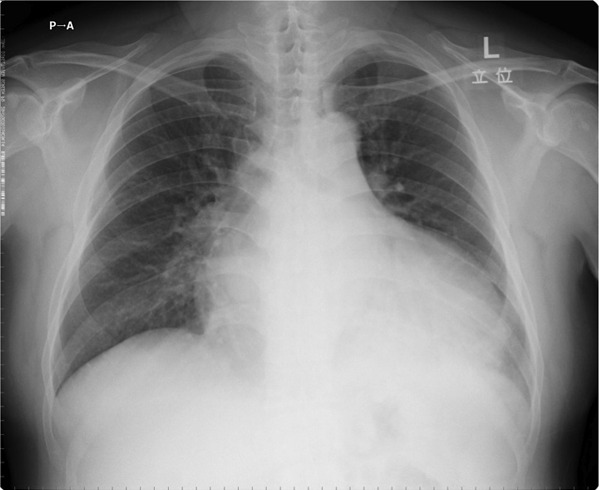

問題の心電図は洞頻脈、V1で典型的な左房負荷の所見を認め、左室の電位は高く、左室誘導(I、aVL、V5−6)でsagging型のST低下とT波の逆転を認める。典型的な圧負荷に対する左室肥大の所見である。左房負荷の存在から長期間の圧負荷と左心不全の存在が示唆される。来院時の身体所見は、血圧が高く頻脈。心臓では3音、4音がsummation gallopとして聴取されている。急性左心不全による肺水腫の状態である。胸部X線では、心陰影は拡大、左室の拡大と肺血管の再分布を認める。

胸部X線画像